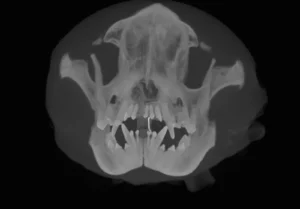

With this CT imaging system the entire head can be imaged in a single 18 second scan, allowing evaluation of teeth, jaw bones, maxillofacial anatomy, sinus and nasal cavities. CT images are composed of slices which allows millimeter by millimeter detailed assessment. In addition, a computer-generated three dimensional image may be produced. These images are superior to regular x-rays for evaluation of maxillofacial fractures, temporomandibular joint dislocations, and oral cancer.

Sample Images